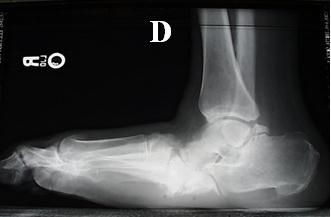

Figure 1C

The patient's normal-appearing left foot radiograph (

C

) is shown in comparison with his right foot radiograph (

D

), which reveals consolidation of the osseous fragments creating the chronic joint subluxation and bony prominence on the bottom of midfoot. Figure 1D

Also seen in Figure 1 are a normal-appearing radiograph of a patient’s left foot and, for comparison, a radiograph of the patient’s right foot showing consolidation of the osseous fragments creating the chronic joint subluxation and bony prominence on the bottom of the midfoot.